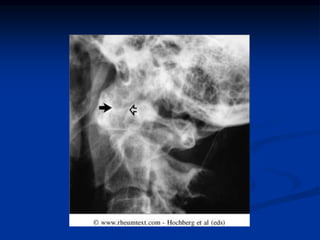

 Don’t forget the cervical spine!!

Instability at cervical spine can lead to

impingement of the spinal cord.

 CNS- peripheral neuropathy, cord-compression

from atlantoaxial/midcervical spine subluxation,

entrapment neuropathies